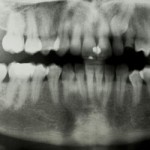

Рентгенография зубов

Рентгенография зубов – метод исследования, направленный на получение снимка зуба и полости рта. Рентгеновские лучи – вид электромагнитного излучения; такие лучи способны проникать сквозь...